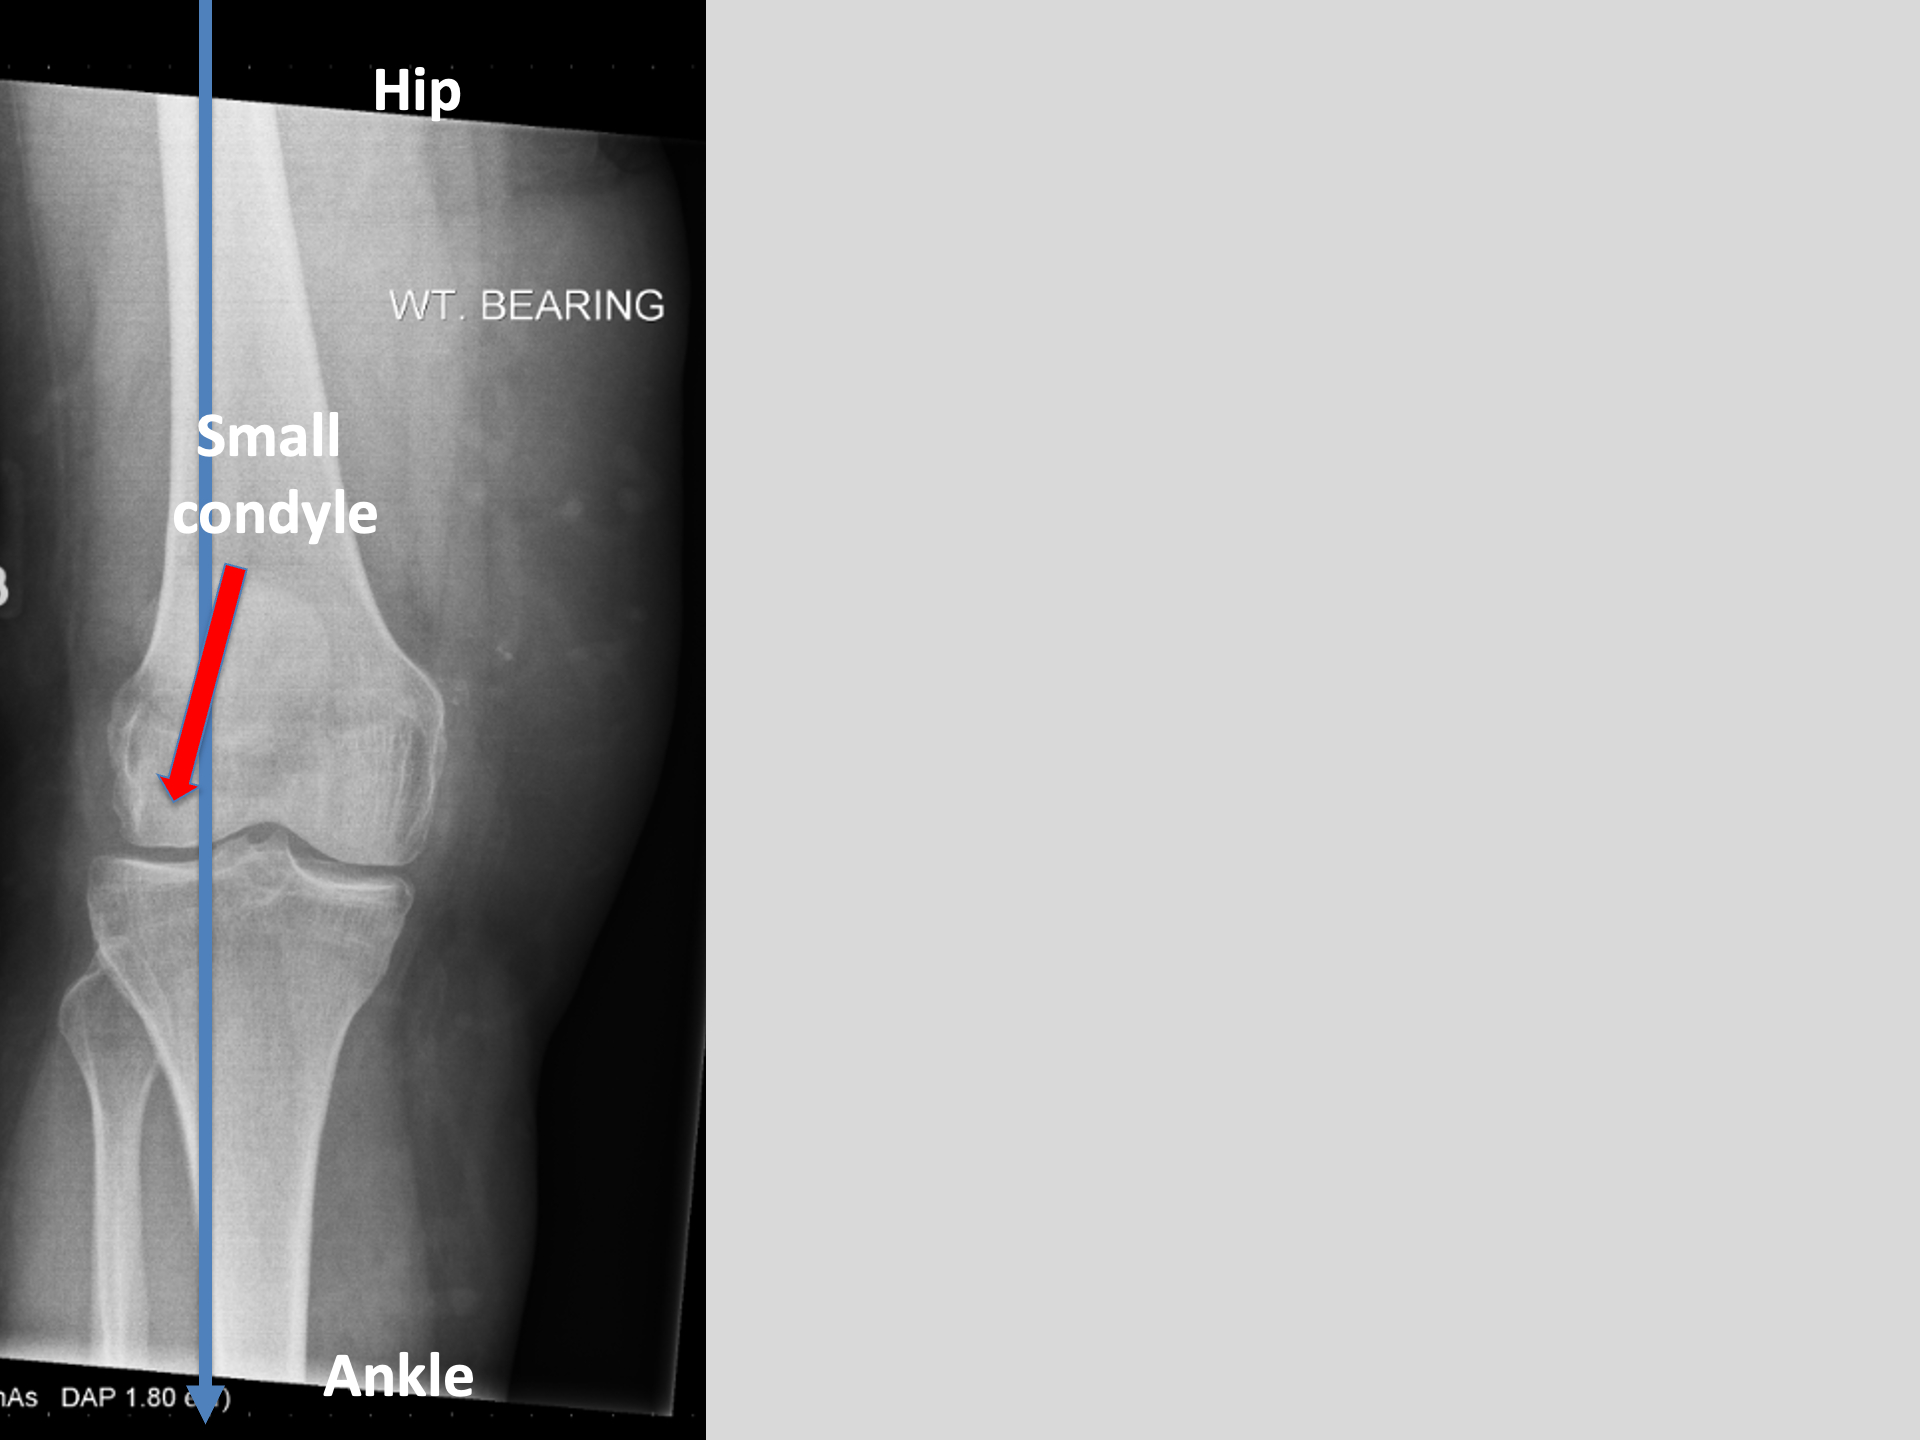

That blue line is way out to the outside of Marie's right knee

Every step is jamming all the force through the outside of her knee.

BUT, when it gets to this point..

This level of deformity (see 3.)

That knee is not getting better.

AND is likely to get worse.